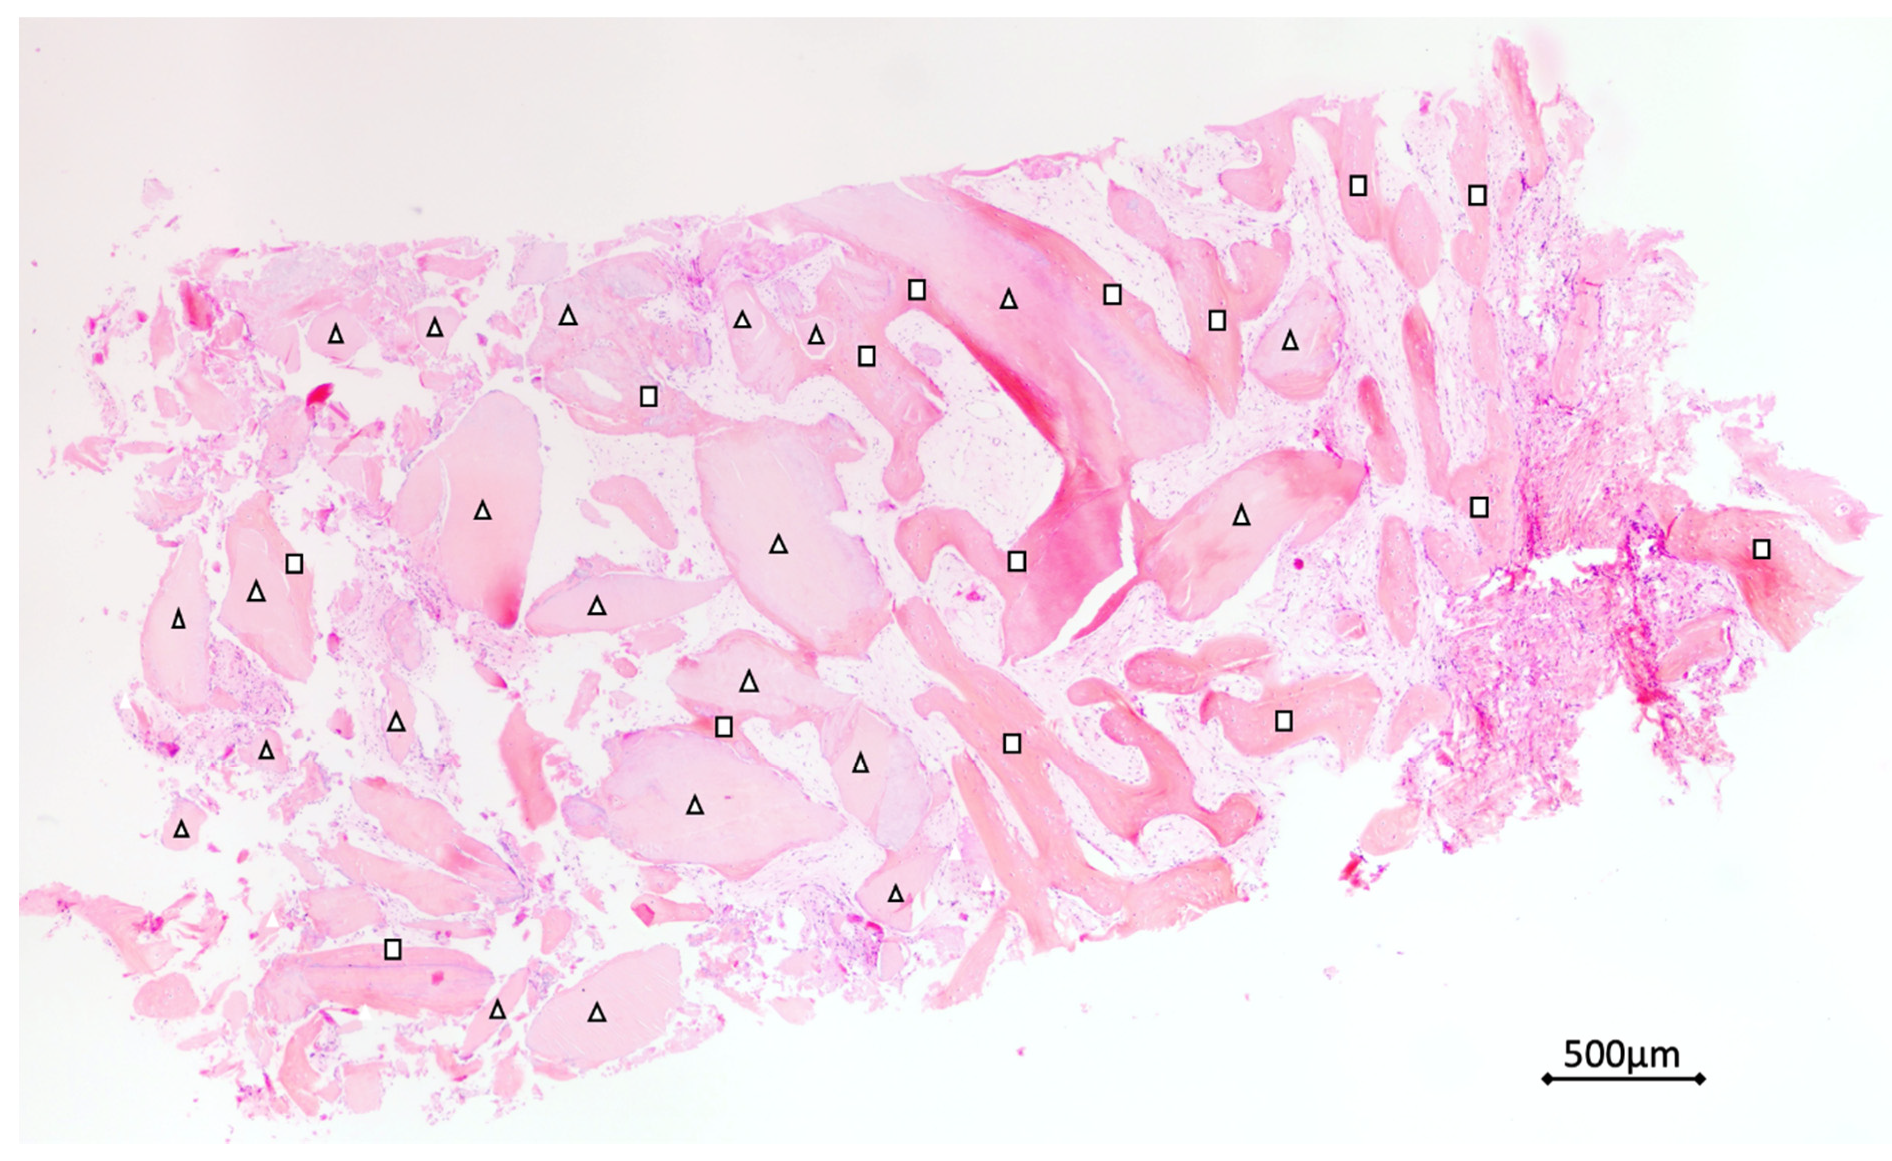

3.3. Histological Analysis